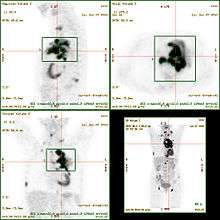

The standardized uptake value (SUV) is a nuclear medicine term, used in positron emission tomography (PET) imaging for a (semi)quantitative analysis.[1] Its use is particularly common in the analysis of [18F]fluorodeoxyglucose ([18F]FDG) images of cancer patients. It can also be used with other PET agents especially when no arterial input function is available for more detailed pharmacokinetic modeling. Otherwise measures like the fractional uptake rate (FUR) or parameters from more advanced pharmacokinetic modeling may be preferable.

The cimg data may be the pixel intensities of a calibrated PET image. Calculated SUV data can then be visualized as parametric SUV image. Alternatively, groups of such pixels may be selected e.g. by manually drawing or otherwise segmenting a region of interest (ROI) on the PET image. Then e.g. the average intensity of that ROI may be used as cimg input to calculate SUVs.

The SUV can be significantly affected among other things by image noise, low image resolution and/or user biased ROI selection.[5] For the semiquantitative analysis of [18F]FDG uptake in tissue or tumor, several corrections have been recommended (see [6] and references therein).